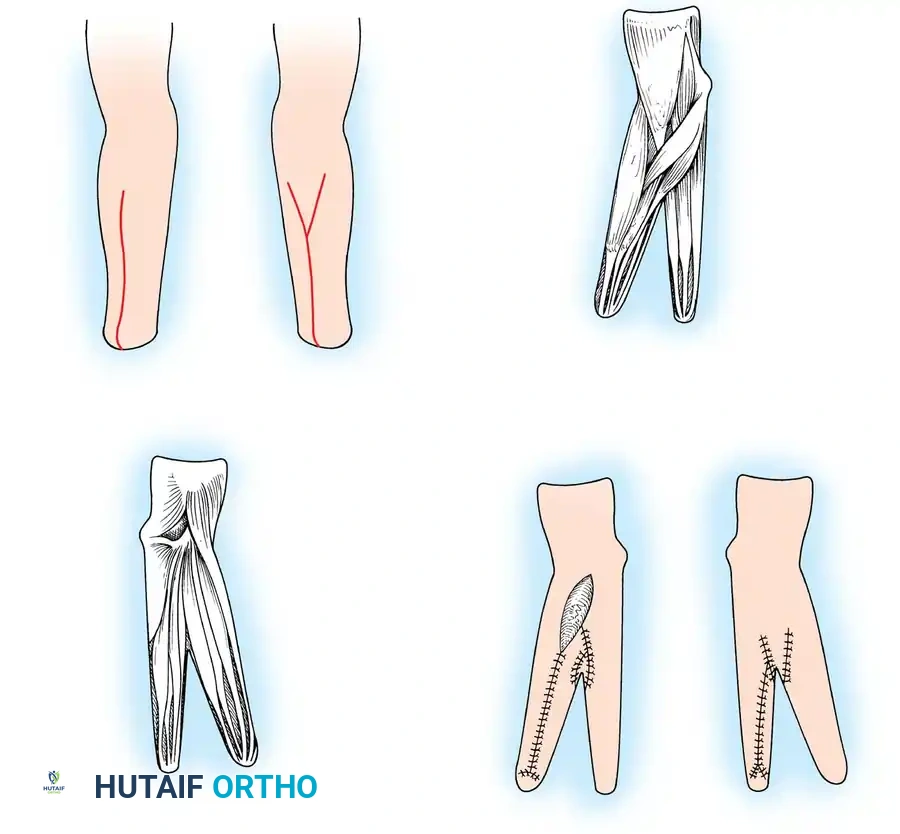

- Incision and Flap Design: Make a longitudinal incision on the flexor surface of the forearm, biased slightly toward the radial side. Make a corresponding incision on the dorsal surface, biased toward the ulnar side. On the dorsal surface, elevate a V-shaped flap to form the new web space at the proximal junction of the rays.

- Skin Coverage: Excise excess subcutaneous fat. Rotate the skin around each ray and close it so that the suture lines do not lie on the opposing (contact) surfaces of the pincers. Apply split-thickness skin grafts to any remaining defects, ensuring the tactile contact surfaces are covered by sensate, full-thickness skin.

- Closure and Drainage: Suture the dorsal V-flap into the proximal junction to create the web. Insert small rubber drains, obtain meticulous hemostasis after tourniquet deflation, and apply a bulky compression dressing with the rays separated by at least 6 cm.

- Incision: Make a curved, horseshoe-shaped incision around the dorsal, radial, and volar aspects of the base of the thumb.

- Flap Elevation: Undermine the skin distally, staying strictly superficial to the main venous drainage network to prevent venous congestion and subsequent flap necrosis. Continue undermining until a hollow, thimble-like flap has been elevated and slipped off the end of the bony stump. The blood supply to this flap is maintained via the arborization of vessels around the base of the index finger in the thumb web.